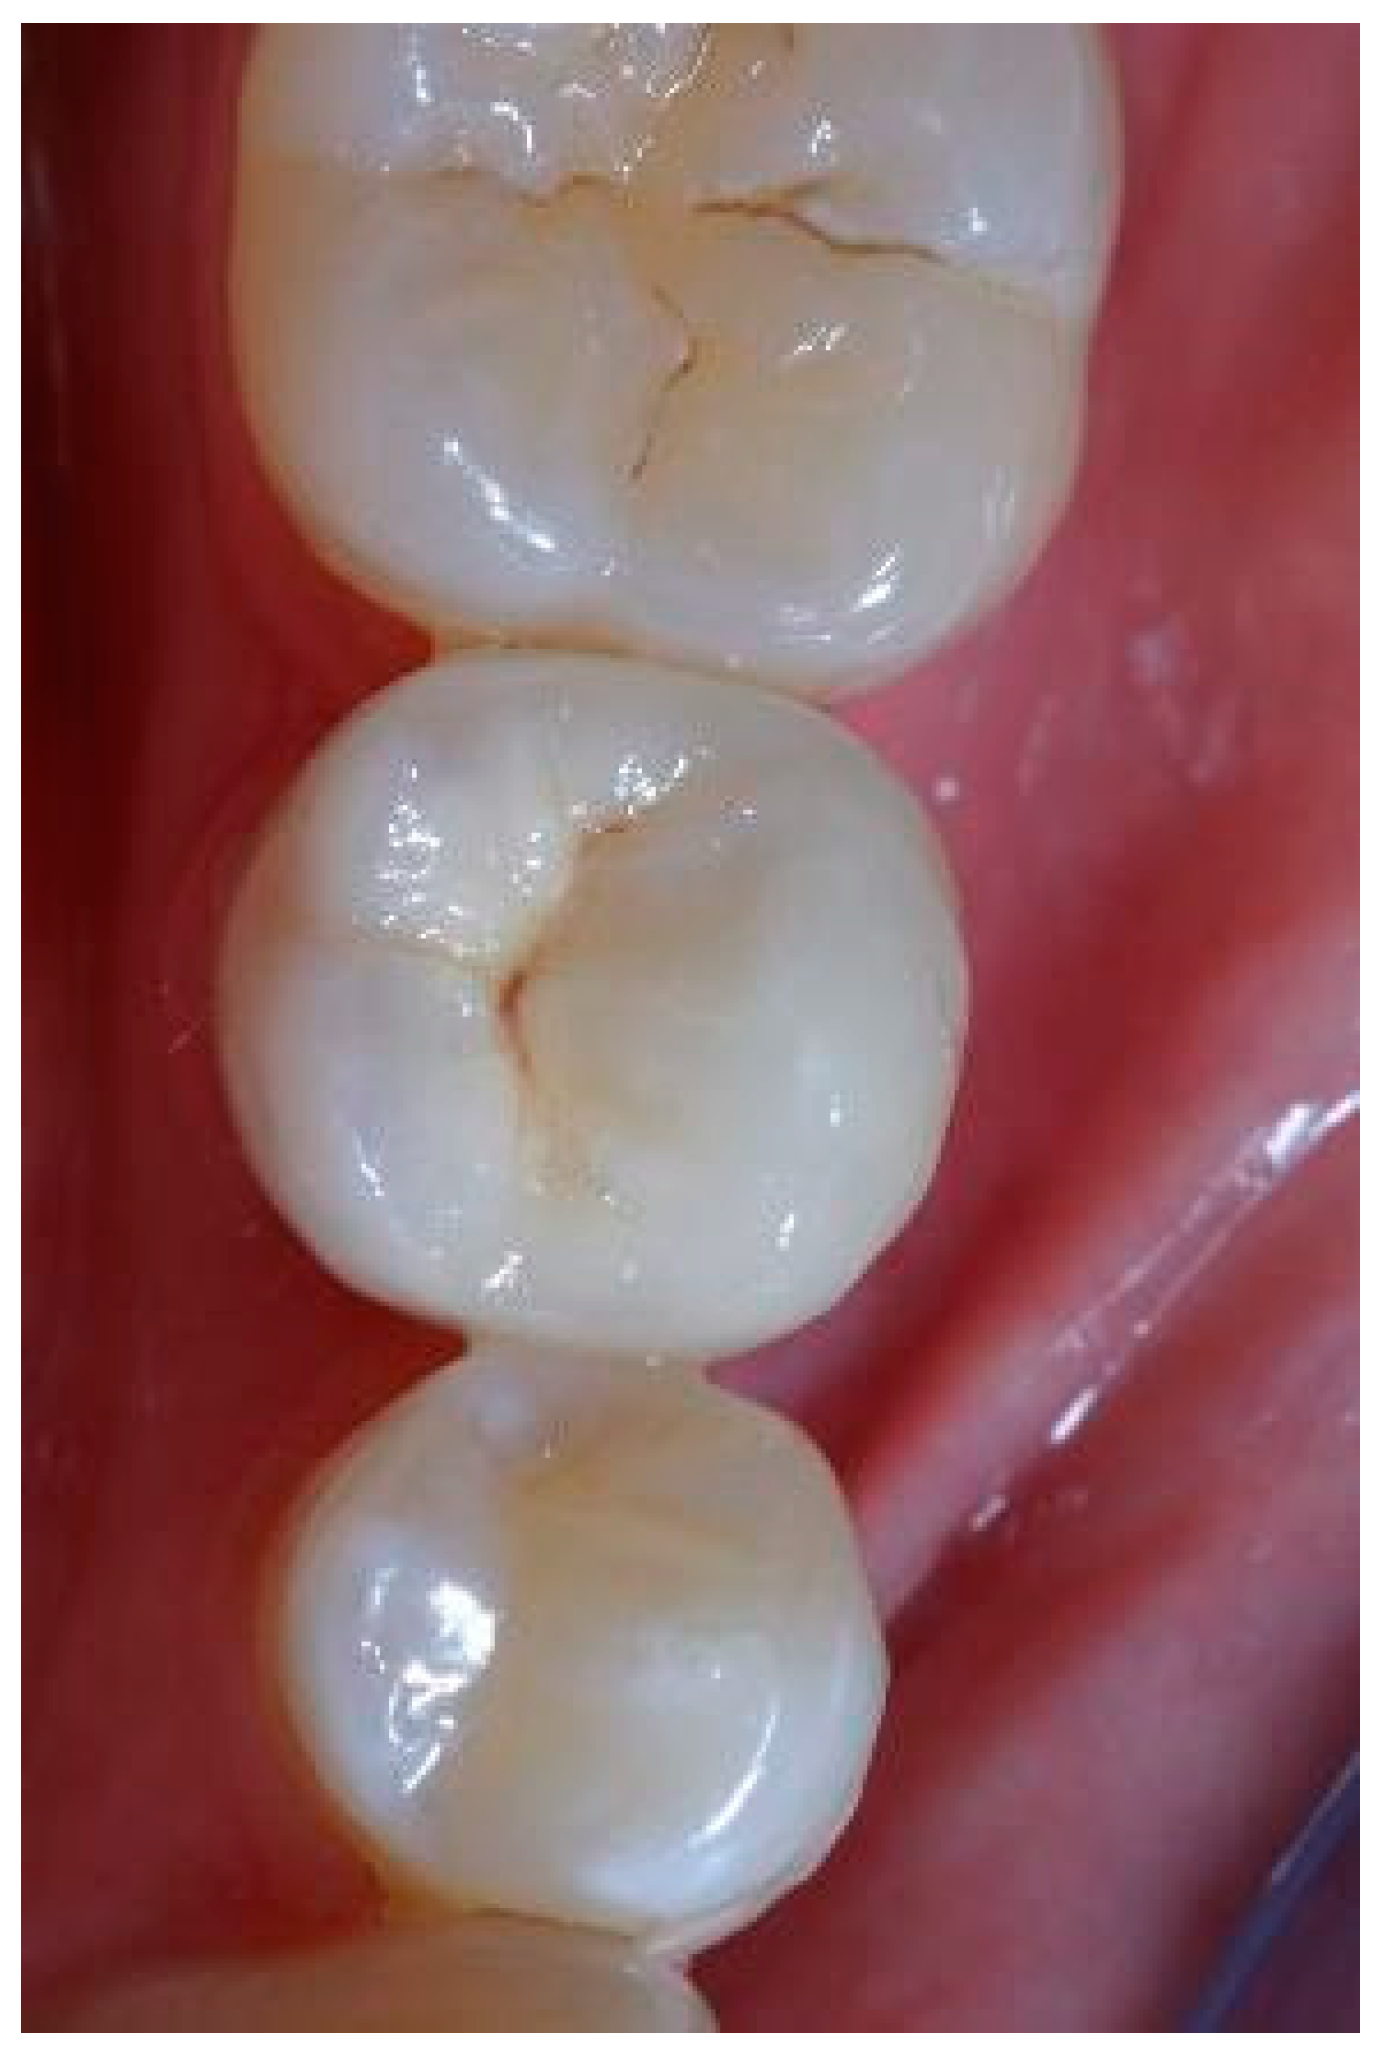

Figure A13.

Figure A16.

Figure A19.

Figure A20.

Figure A22.

Figure A23.

Clinical situation at the 5-year follow-up. Lateral view.